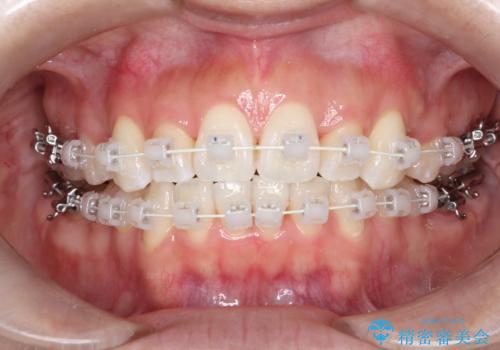

【審美装置】前歯のがたがたを治したい

- 矯正装置

- 審美装置

- 前歯の凸凹と口元の突出感を主訴に来院されました。

臼歯関係が上顎前突傾向のため、上の小臼歯を抜歯してワイヤー矯正を行なっております。

下顎の叢生はIPRを行なって配列しています。